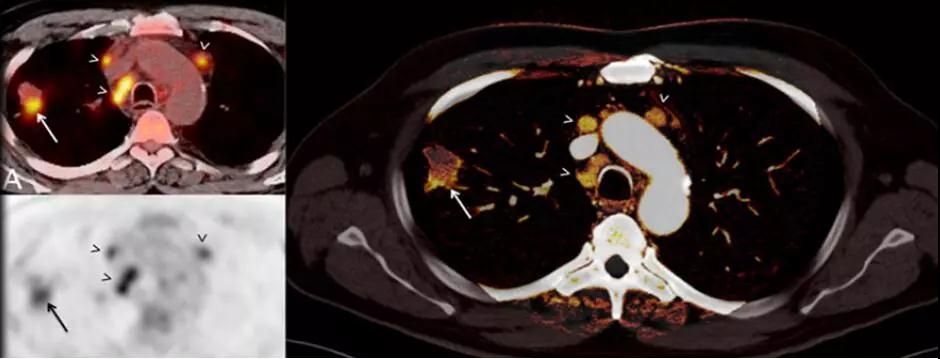

7. 類PET 成像:

傳統PET成像存在輻射劑量過高、放射污染、價格昂貴等局限性。

SOMATOMForce的純譜雙能量成像技術具有更好的靈敏度和特異性,使CT雙能量的應用上升到一個前所未有的水平,應用范圍更廣泛,不但可以常規對腫瘤組織類型、心血管疾病進行更為精確的識別,更是突破影像界限,首次實現碘、鈣、水、脂肪、鐵等多物質多元素多參數量化成像,能夠精準評估骨髓挫傷水腫、腫瘤浸潤活性。

△提高診斷準確性-肺結節能量碘圖